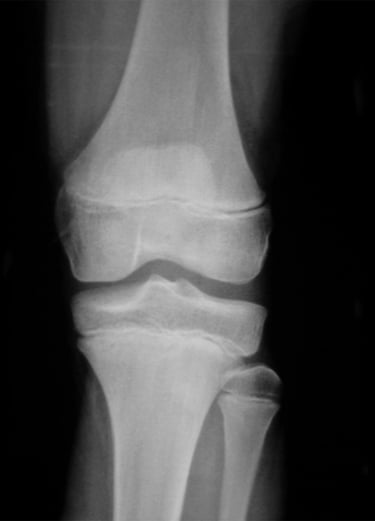

Gydytojas Markas Fiodorovas - ortopedas traumatologas, sporto traumų specialistas, sukaupęs 20 metų patirtį tausojančioje artroskopinėje chirurgijoje. Daugiau nei 650 artroskopinių kelio, peties ir kitų sąnarių operacijų per metus atliekantis chirurgas, taip pat aktyviai įsitraukęs į mokslinę veiklą. Gydytojas yra nuolatinis tarptautinių konferencijų lektorius bei tarptautinis artroskopinės chirurgijos instruktorius.